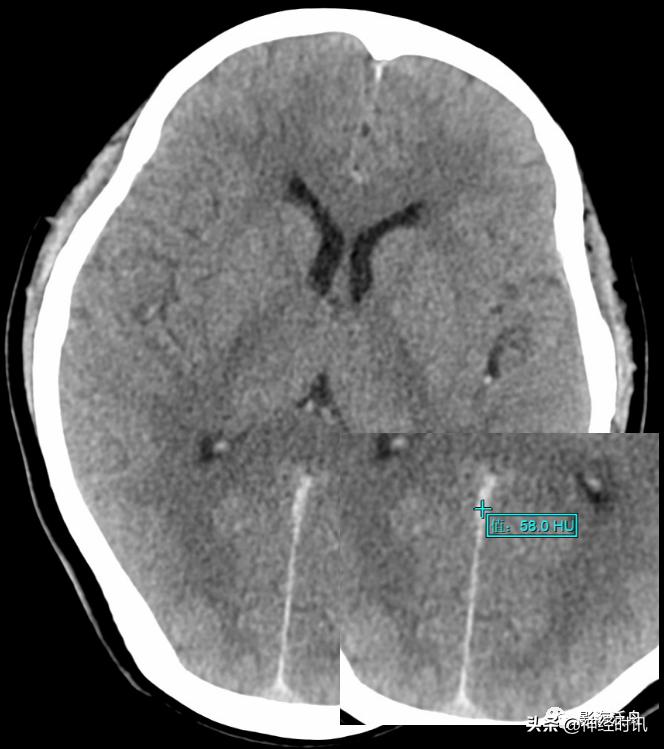

由于脑脊液的流动冲刷作用,蛛网膜下腔少量出血所形成的小血肿远没有脑实质内的血肿稳定,即便在外伤后第一个24h内,其CT值也很难超过60HU(课本上讲的脑内血肿极限CT值为94HU,平时工作中当然不可能遇到,但70+HU的血肿还是很常见的)。所以诊断少量蛛血的最佳时间是在外伤后第一个24h内,一旦超过24小时其CT值就会快速衰减,3天以后基本上很难在CT平扫上看到高密度影。

典型的大脑镰前部少量蛛血,血肿的边缘毛糙(红箭)且抵达胼胝体膝部的前缘(黄箭头)。4天后复查头颅CT平扫,相应部位少量蛛血基本吸收。

另一例表现类似的大脑镰前部少量蛛血,血肿的边缘总是有一种毛毛糙糙的感觉(红箭)。

大脑镰前下部极少量蛛血(红箭),淡黄色虚线框勾勒出胼胝体膝部,血肿的边缘仍然是 模模糊糊的,注意这幅图中双侧大脑半球见多发斑点状高密度影(绿箭头),随访证实系伪影所致,而非弥漫性轴索损伤。夜班急诊时CT诊断的难点在于其密度分辨率有限(相较于MR),5mm层厚带来的容积效应干扰,有时候再加上噪声形成的伪影,就非常考验平时的基本功以及经验积累了。

国内一些文献将大脑镰一侧不对称的高密度影被定义为“偏密征”,并认为上述影像学特征是诊断大脑镰旁少量蛛网膜下腔出血的可靠征象,可提示出血部位位于“偏密征”附近,或继发于邻近的其它颅内损伤。

本例颅脑外伤患者的大脑镰右旁可见“偏密征”,但这个血肿的边缘非常光滑(红箭)且未延伸至邻近脑沟内,边缘似乎还带有一些张力感,笔者觉得此例诊断为大脑镰旁硬膜下血肿更合适。但不管怎么说,“偏密征”用于鉴别是否存在局限性的脑外伤还是很有用的。